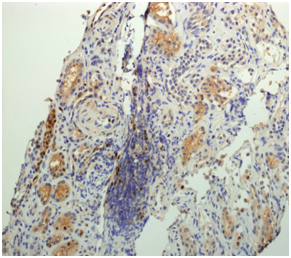

According to local guidelines, treatment with EPOCH-R (rituximab 385 mg/m2 on day 1, etoposide 103mg/m2 on days 1-4, prednisone 130mg/m2 on days 1-5, vincristine 0.6mg/m2 on days 1-4, adriamycin 20mg/m2 on days 1-4 and cyclophosphamide 1,540mg/m2 on day 5 ), along with prophylaxis for Tumoral lysis syndrome were administered. On the fifth day after chemotherapy, the patient developed renal function impairment with macroscopic haematuria containing dysmorphic erythrocytes, increase of serum creatinine, and proteinuria up to 6.37 mg/dl and to 3.5 g/24 hours, respectively. Serum phosphates, calcium uric acid, fibrinogen, and coagulation tests were normal. Thrombosis of the renal vein or extrinsic compression by lymphadenopathy was rule out by renal ultrasonography. Flow cytometry analysis of the urine sample disclosed the presence of clonal lymphocytes with MCL phenotype. The transjugular renal biopsy examination showed mesangialhypercelullarity, thickening of capillary basal membranes, some fibrocelullar crescents (Figure 1a); moderate intimal fibrous thickening of medium and small caliber arterioles (Figure 1b); and focal intersticial infiltration by atypical lymphoid B cells cyclin D1 positive (Figure 2). The tonsil biopsy showed positive immunohistochemical staining of the cycline D1 (Figure 3).

Figure 2 Focal intersticial infiltration by atypical lymphoid cells cycline D1 positive in the renal biopsy.

Figure 3 Positive inmunohistochemical staining of the cycline D1 of the tonsil biopsy.